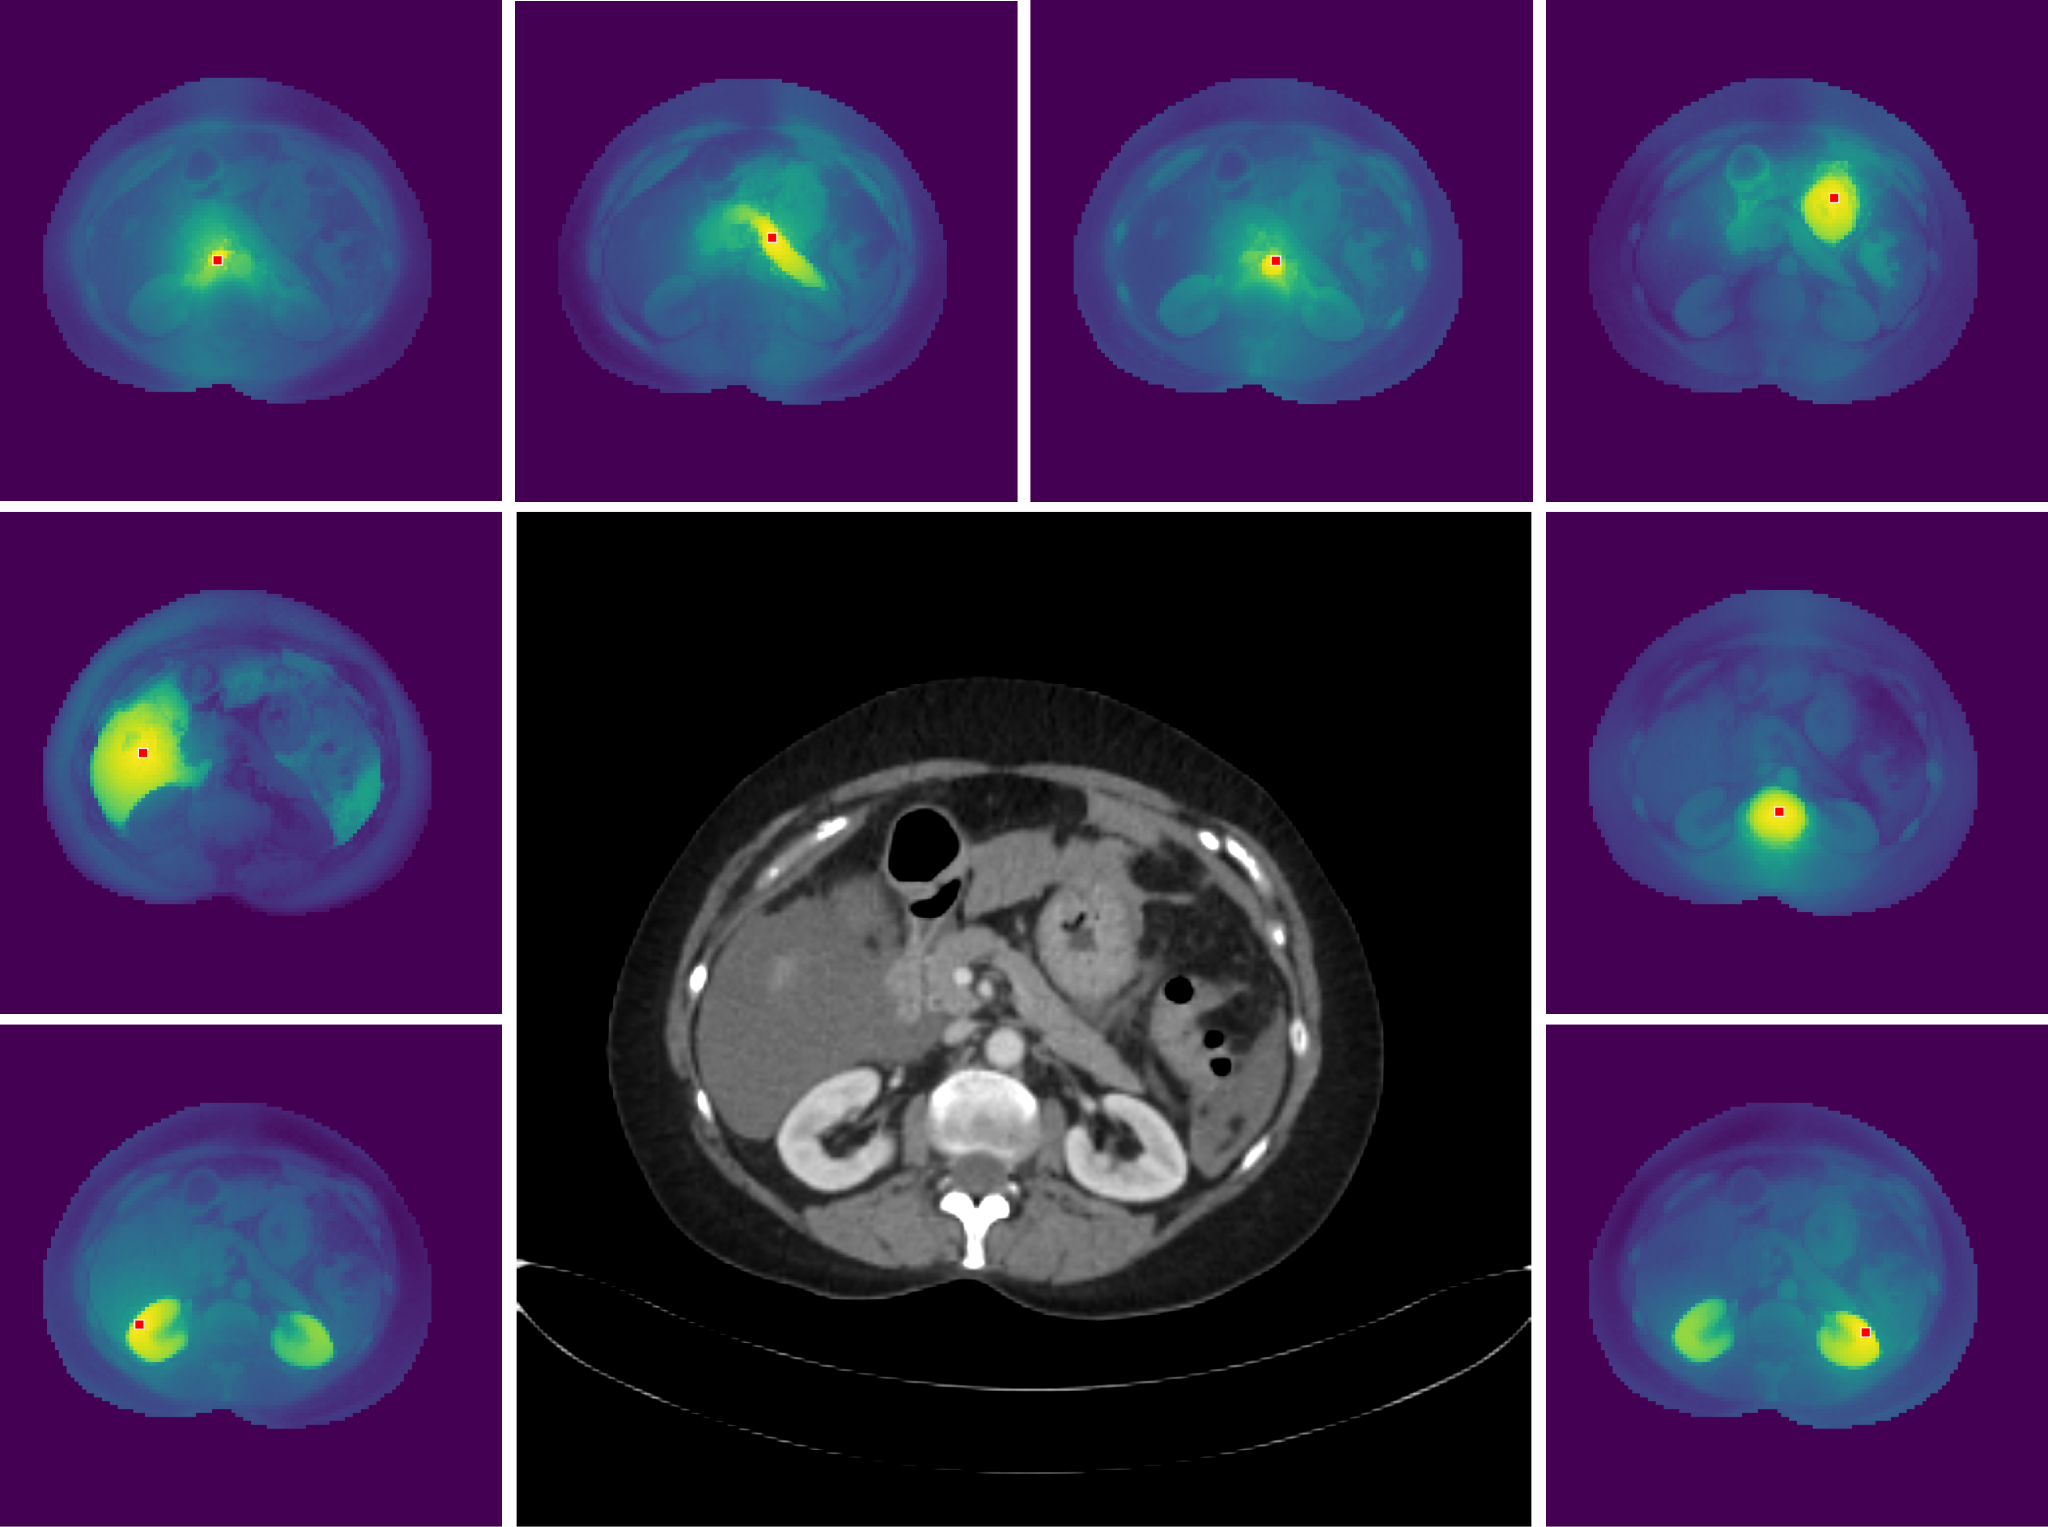

MedDINOv3: How to adapt vision foundation models for medical image segmentation?

A vision foundation model that works effectively on medical images and outperforms specialized medical systems on several benchmarks. MedDINOv3 adapts DINOv3 to medical segmentation through domain-adaptive pretraining on 3.87M CT slices, showing strong results across four segmentation benchmarks. The key breakthrough is multi-scale token aggregation combined with a multi-stage training recipe that helps bridge the domain gap between natural and medical images.